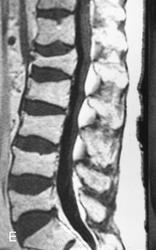

ГМ. СМ. Миеломная болезнь (множественная плазмоцитома). +

Миеломная болезнь (множественная плазмоцитома).

Лия А. Moulopoulos и Мелетий А. Dimopoulos